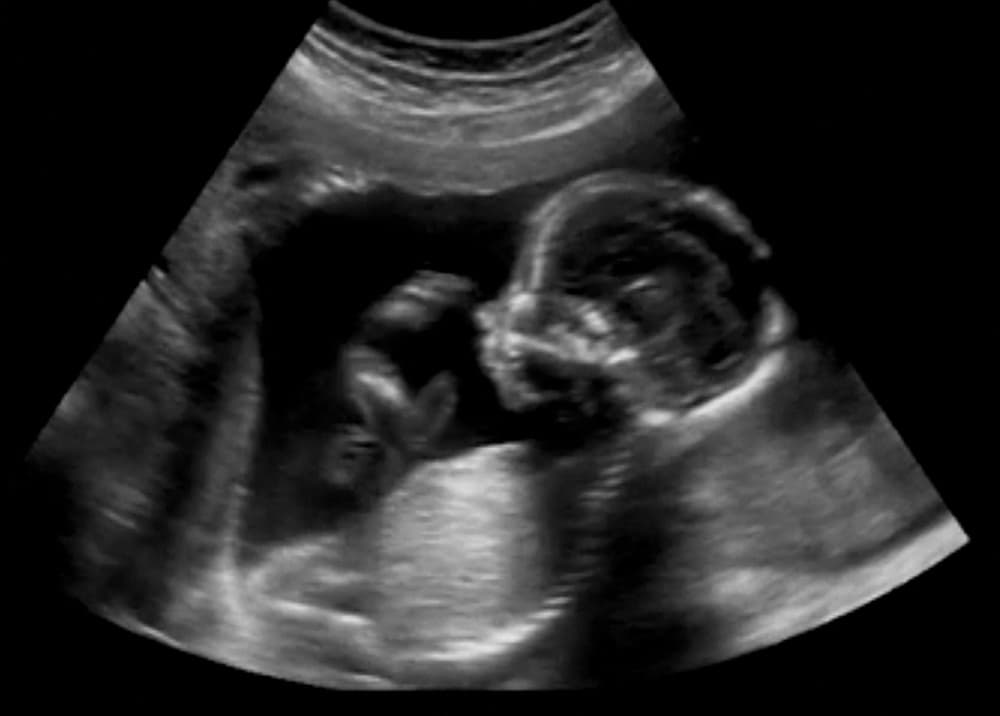

Se buscó medir la respuesta del bebé frente a la voz materna in situ, al tacto materno del abdomen o ante ningún sonido ni tacto, utilizando una sonografía 3D a tiempo real para controlar la respuesta de los fetos.

Lo que encontraron es que cuando las madres tocaban sus panzas, los fetos movían los brazos, la cabeza y la boca. En cambio, cuando las madres hablaban o no hacían nada, ninguno de estos movimientos se destacaron.